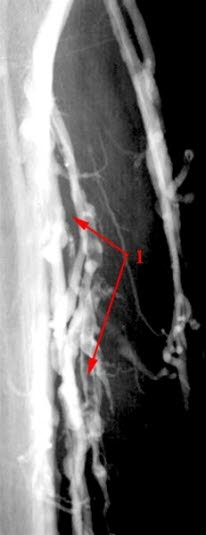

Trombe i en av leggens dype vener (1)

Tromben framstår som oppklaring sentralt i venen med kontrast langs veggen